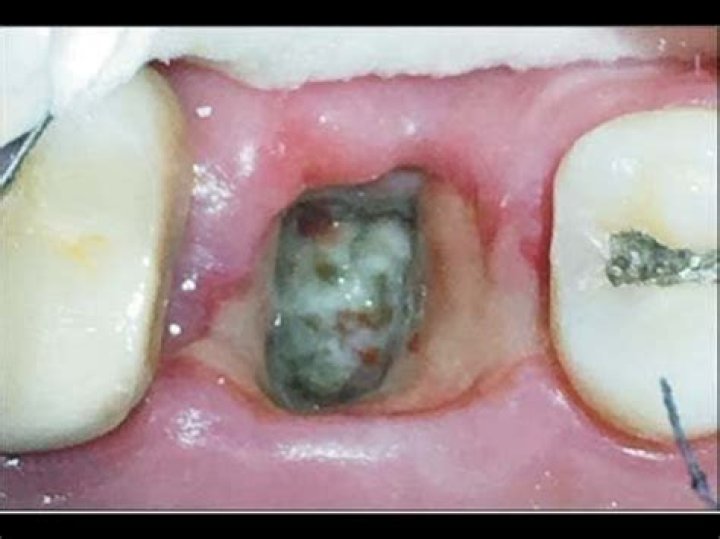

What color is dry socket?

Is dry socket GREY?

What does a dry socket look like vs normal?

• visibly empty socket with missing or partially missing blood clot.

• visible bone in the socket.

What is the white stuff in my tooth extraction site?

A blood clot develops over the extraction site. Shortly after, you will see white stuff form around the tooth socket. If you are not in any pain, this is a good sign. It means that the white stuff is something called granulation tissue, that replaces the clot in the extraction site as the wound begins to heal.